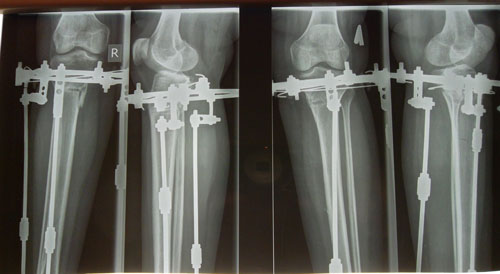

Дата операции 16.06.2014г.

Дата снятия аппаратов 04.11.2014г.

Срок лечения 138 дней.

рентген в день снятия аппаратов.